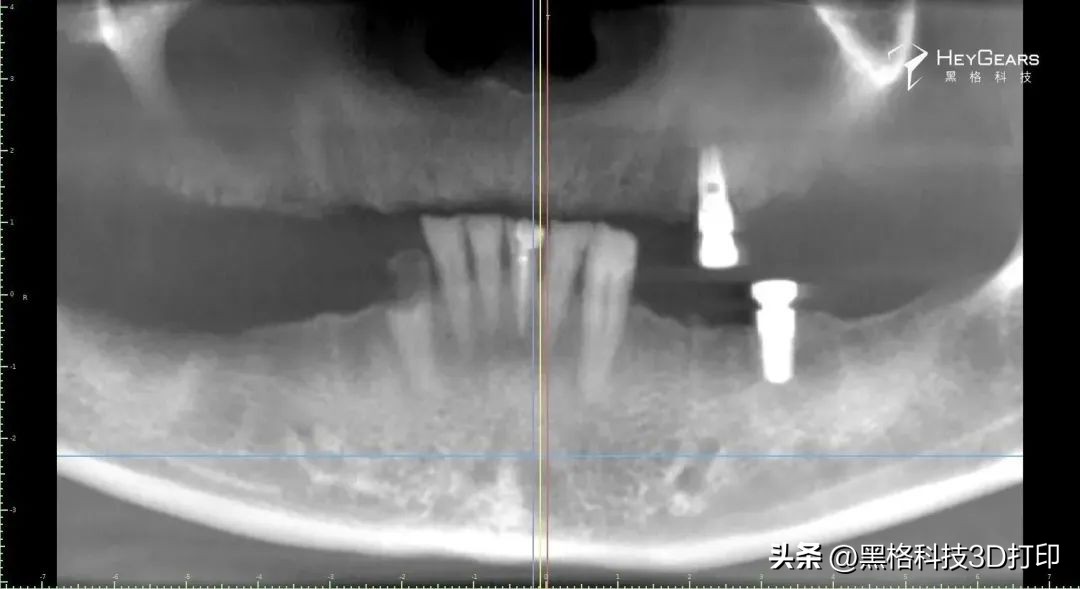

·影像学检查:

▲术前CBCT